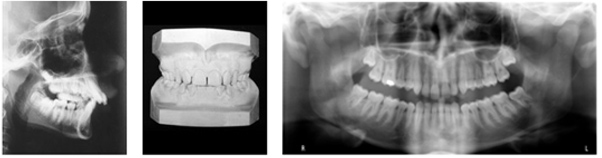

Meghatározzuk, hogy szükség van-e fogszabályozó kezelésre, és ha igen, akkor mikor érdemes azt elkezdeni. A pontos diagnózishoz szükség van egy panorámafelvételre és egy teleröntgenre, amelyeken az összes fog koronája, gyökere, az állkapocsízület és a csontok láthatók, illetve egy-egy lenyomatra az alsó és felső állcsontról.

Az utóbbiból készített gipszmintán pontosan kimérhető a fogak és az állcsontok viszonya. Emellett több irányból is fényképeket készítünk a páciens arcáról, illetve fogairól.